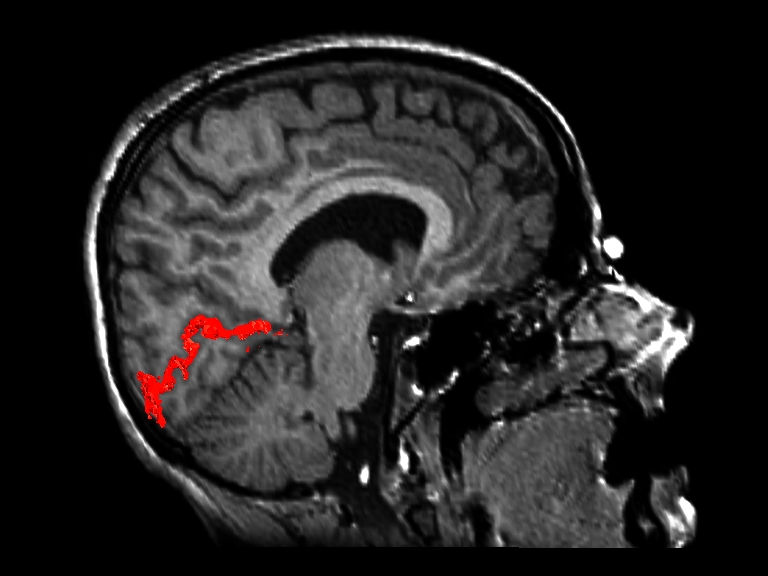

The following image indicates the location of the reconstructed surface (in red) in the brain.

Visual Cortex Reconstruction in a Sagittal MR Slice

A computer animation scrolls through sagittal MR images surrounding the reconstructed calcarine fissure and grey matter (QuickTime format, 2.8Mb).